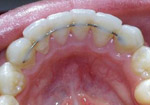

Permanent Fixed Retainers

An entirely different category of orthodontic retainers are fixed retainers. A fixed retainer typically consists of a passive wire bonded to the tongue-side of the (usually, depending on the patient's bite, only lower) incisors. Fixed retainers cannot be removed by the patient. Some doctors prescribe fixed retainers regularly, especially where active orthodontic treatments have affected great changes in the bite and there might a high risk for reversal of these changes.